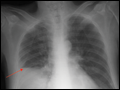

| Figure e34-1 Normal chest radiograph—review of anatomy.1. Trachea. 2. Carina. 3. Right atrium. 4. Right hemidiaphragm. 5. Aortic knob. 6. Left hilum. 7. Left ventricle. 8. Left hemidiaphragm (with stomach bubble). 9. Retrosternal clear space. 10. Right ventricle. 11. Left hemidiaphragm (with stomach bubble). 12. Left upper lobe bronchus. | |